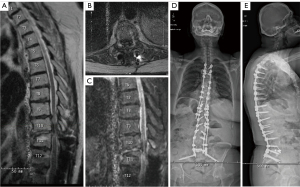

Imaging demonstrated an expansile lesion consistent with metastasis involving the T6 and T7 vertebral bodies and pedicles causing high grade epidural spinal cord compression (ESCC) and thoracic stenosis (Figure 2A-2C). Examination on arrival to the operative hospital confirmed absent BLE strength, T7 sensory level, and American Spinal Injury Association (ASIA) B impairment rating (3,4). Based on the spinal instability neoplastic score (SINS) and high grade ESCC with ASIA B neurologic rating, separation surgery and stabilization was recommended (5,6). The patient was indicated for T5–T7 posterior and transpedicular thoracic decompression, T4–T9 posterior instrumented fusion.

Intraoperatively, T4–T9 instrumentation and T5–T7 dorsal decompression was performed with patient in 20-degrees ProAxis flexion to accommodate preoperative thoracic flexion. The thecal sac above and below compression was normal and decompressed to aid in ventral and transpedicular decompression performed at bilateral T6 and left T7. Figure 2D,2E demonstrates standing 5-month postoperative radiographs.